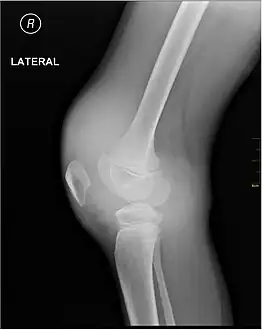

X-Ray- haemoarthritis -

Haemarthrosis on lateral view

Muscle and joint haemorrhages – or haemarthrosis – are indicative of haemophilia,[11] while digestive tract and cerebral haemorrhages are also germane to other coagulation disorders.

Repeated bleeds into a joint capsule can cause permanent joint damage and disfigurement resulting in chronic arthritis and disability. Joint damage is not a result of blood in the capsule but rather the healing process. When blood in the joint is broken down by enzymes in the body, the bone in that area is also degraded, this exerts a lot of pain upon the person afflicted with the disease.[12][13][14]